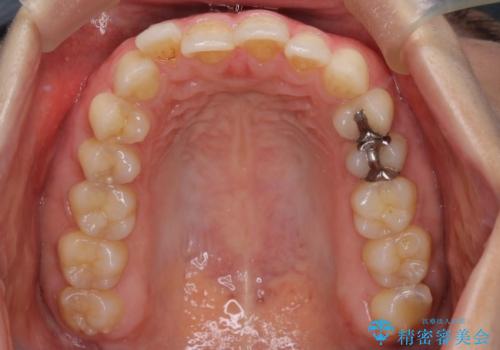

【下顎前歯の抜歯矯正】マウスピース矯正

- 下顎前歯の叢生を主訴に来院されました。

臼歯関係の状態から下顎前歯一本の抜歯を行う治療計画を立て、インビザラインを使用して治療を行いました。

今回の抜歯ケースはインビザラインでも綺麗に治ります。